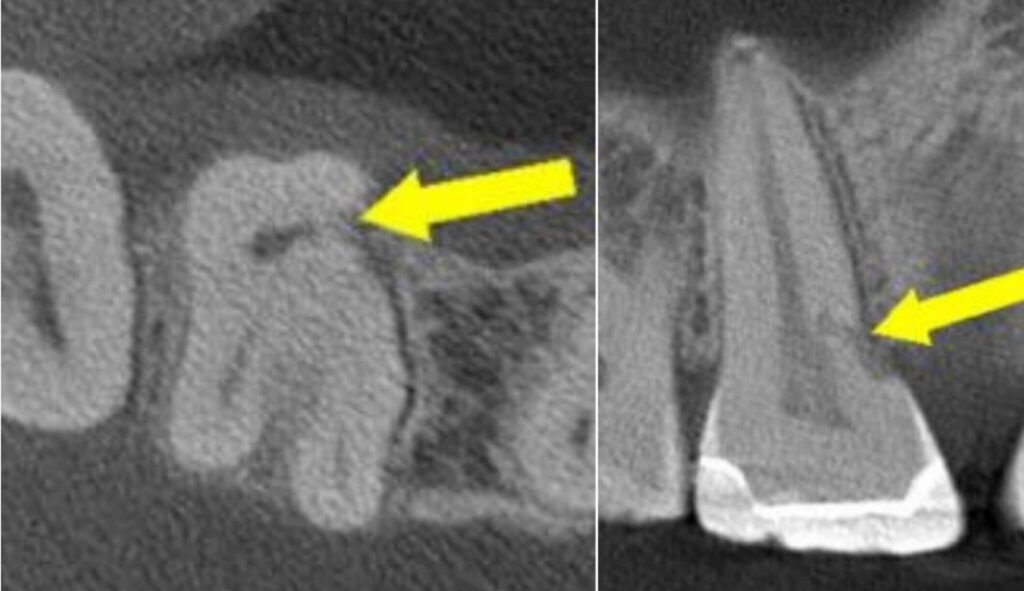

• Cervical resorption (hides right by the gumline, throws on a disguise and pretends to be decay—sneaky little punk)

Cervical resortion: Note the apical extensions and circumpulpal spread

Step one? Diagnosis. CBCT’s your best friend. Periapical radiographs can help, but CBCT? That’s like seein’ the Matrix. Don’t treat what you can’t see.